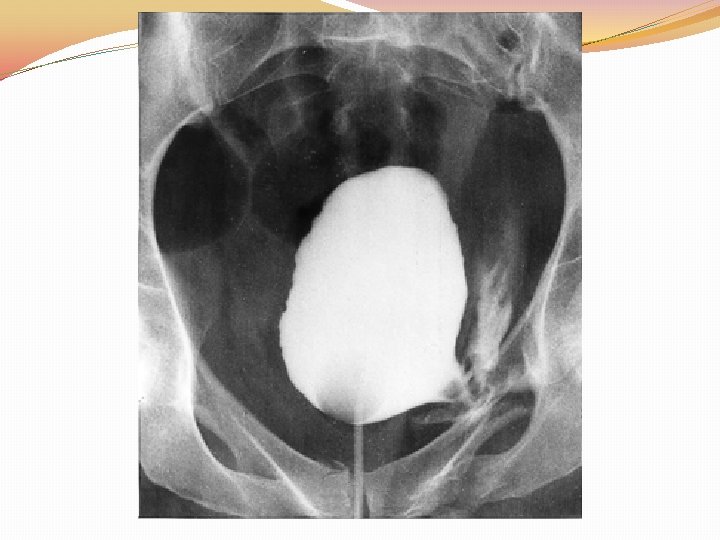

WHAT NEXT? �STEP ONE Foley’s catheter �STEP TWO x ray/ CT scan/cystography

MANAGEMENT �Simple catheter drainage (ie, urethral or suprapubic). �Leave the catheter in for 7 -10 days and then obtain a cystogram. � Approximately 85% of the time, the laceration is sealed and the catheter is removed for a voiding trial. �Almost all extraperitoneal bladder injuries heal within 3 weeks.

MANAGEMENT �If the patient is taken to the operating room for associated injuries, extraperitoneal ruptures may be repaired concomitantly if the patient is stable. �Most, if not all, intraperitoneal bladder ruptures require surgical exploration.